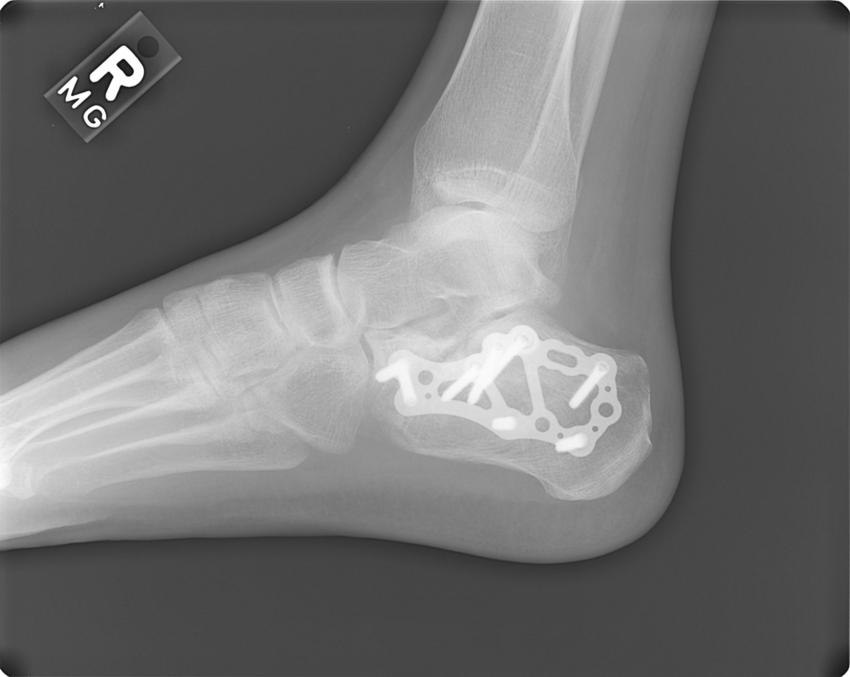

cracked heel

7 screws , steel plate